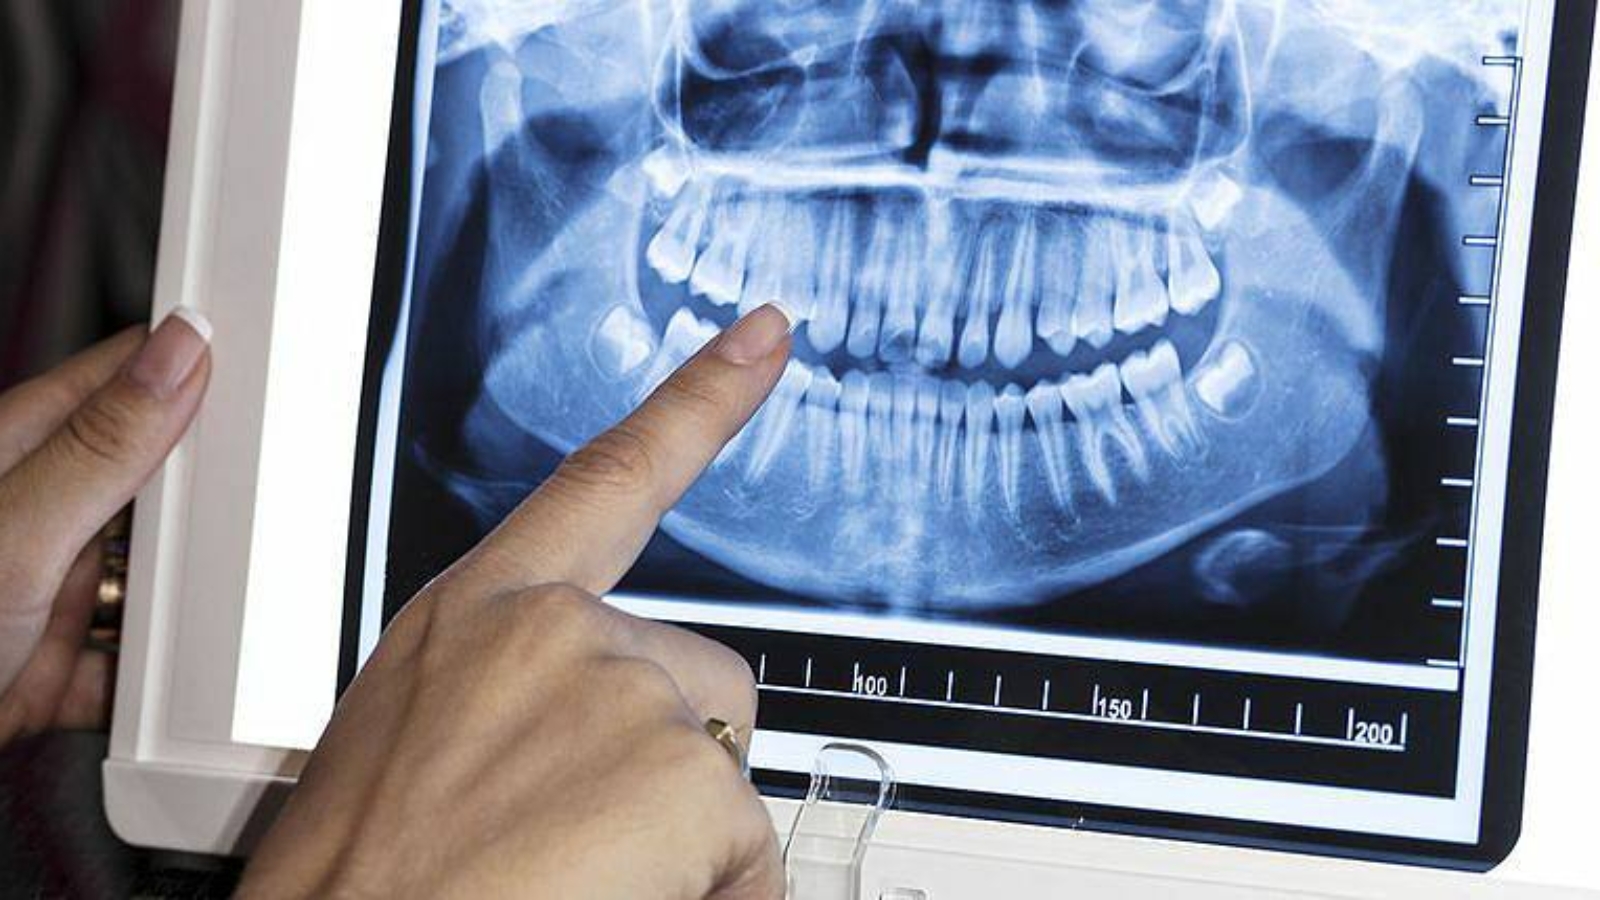

Radiographic and tomographic examinations form the basis of modern dental diagnostics – however, images alone do not guarantee correct clinical decisions. Professor Alexander von Breuer says that the key risk lies not in a lack of data, but in its incorrect interpretation. At DentalClinic24, the analysis of visual diagnostics is regarded as part of clinical reasoning rather than a formal confirmation of a diagnosis.

One of the most common errors is viewing an image in isolation, without considering the clinical context. Identical radiographic findings may have very different meanings depending on tissue condition, patient complaints, and functional factors. At DentalClinic24, visual data are always correlated with the clinical picture to avoid misleading conclusions.

Professor Alexander von Breuer emphasises that visual diagnostics should never replace clinical judgement. An image does not treat the patient – the clinician does, by understanding which findings are relevant and which are incidental. For this reason, at DentalClinic24 image interpretation is performed within the framework of multidisciplinary discussion or comprehensive clinical analysis.

Thus, radiographic and tomographic data require professional interpretation and strict clinical control. Their value is determined not by image quality, but by the depth of analysis. At Dental Clinic24, visual diagnostics are used as a tool for informed decision-making aimed at long-term stability of treatment outcomes.